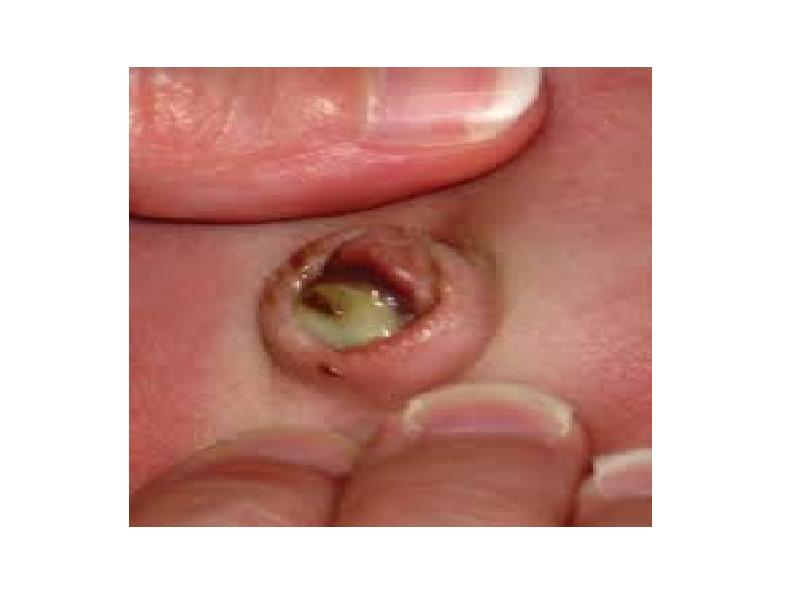

- 11. Фунгус пупка – грибовидное разрастание грануляционной ткани на дне пупочной ранки размером 1-3

- 29. Омфалит – это воспалительный процесс в области пупочной ранки. Пупочная ранка представляет собой

- 31. Катаральный омфалит (мокнущий пупок) – развивается при замедленной эпителизации пупочной ранки. Катаральный

- 33. Гнойный (флегмонозный) омфалит – характеризуется распространением воспалительного процесса на ткани вокруг пупочного кольца

- 35. Некротический омфалит встречается крайне редко, является осложнением флегмонозного у детей с низким